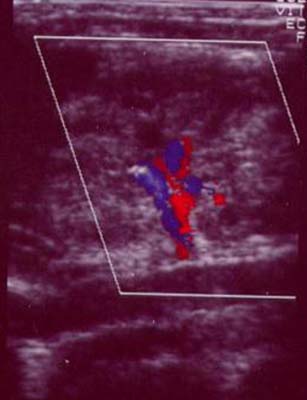

Absence de tronc artériel